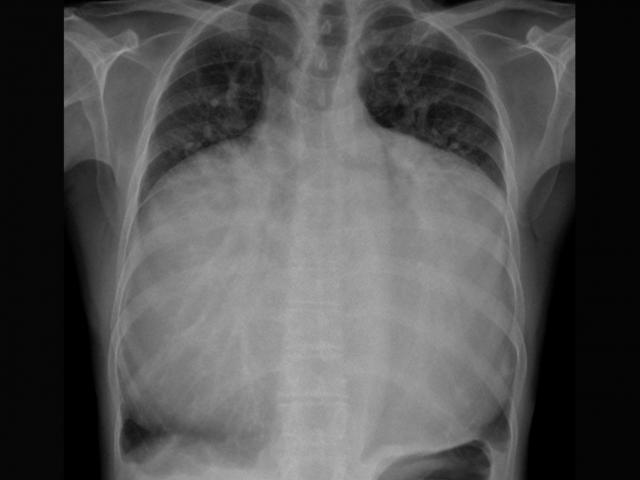

Hình ảnh X-quang một bệnh nhân mắc Hội chứng Pica nuốt lượng lớn đinh, móc sắt vào bụng. Ảnh: Bệnh viện 175.